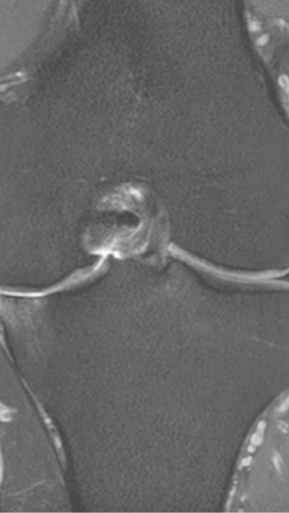

Асептический некроз коленного сустава

4 процедуры ФДТ, 9 процедур MBST, 15 процедур ИПМТ

Параметры изменяются в зависимости от процедуры

Дата публикации: 22.08.2025 14:27:03